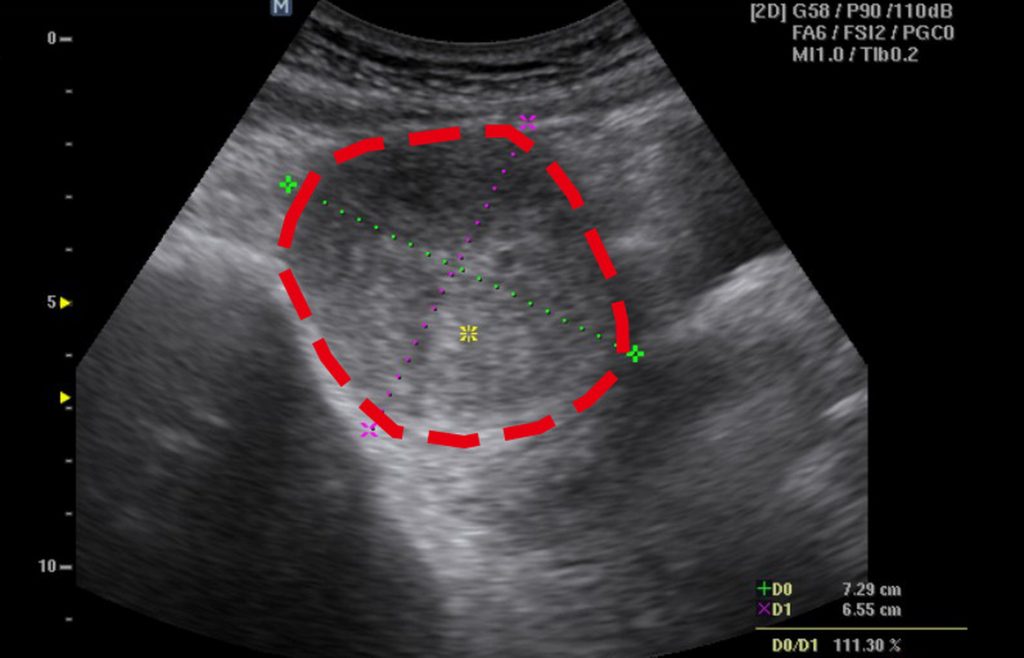

胡洺褘表示,徐女術後恢復良好,住院2天順利出院,1個月後回診,超音波顯示肌瘤已縮小至3.7×3.6×2.9公分,體積僅剩38立方公分,約縮小近9成,肌瘤大小,從芒果變成小番茄,原本困擾多年的經痛及因肌瘤壓迫造成的頻尿、悶脹感,也明顯獲得改善。